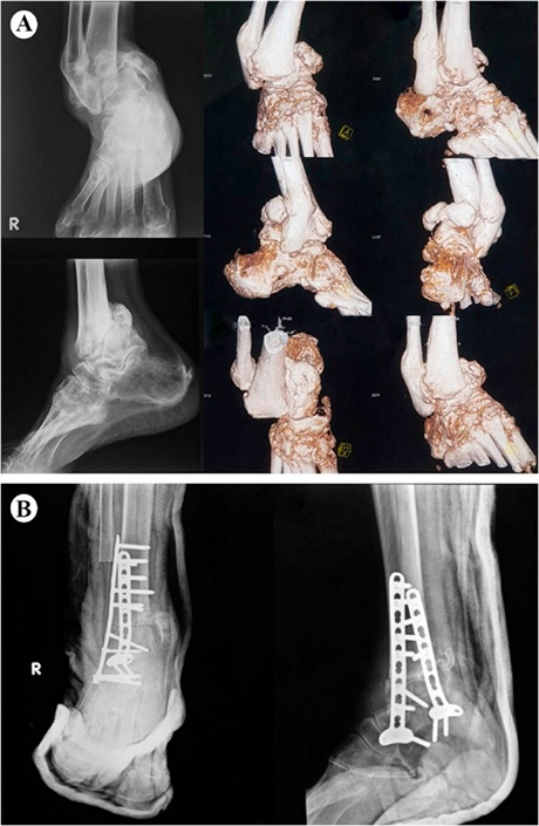

严重的Charcot足,后足骨几乎完全溶解消失

融合手术纠正力线